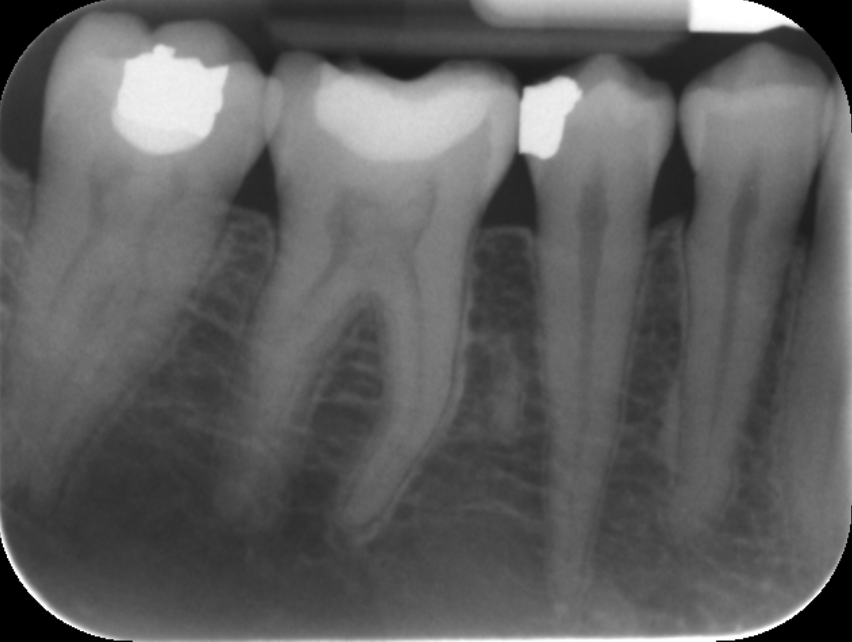

These included team building, communication, photography, endodontics, composite and amalgam restorations, oral surgery, prosthodontics and paediatric dentistry Through these courses I was able to improve on my knowledge and skills from university and implement them in my everyday practice. I have also been keeping a photographic record of my work throughout this year which allows me to reflect on what went well and what I can improve on in the future. space to display your timeline of professional development